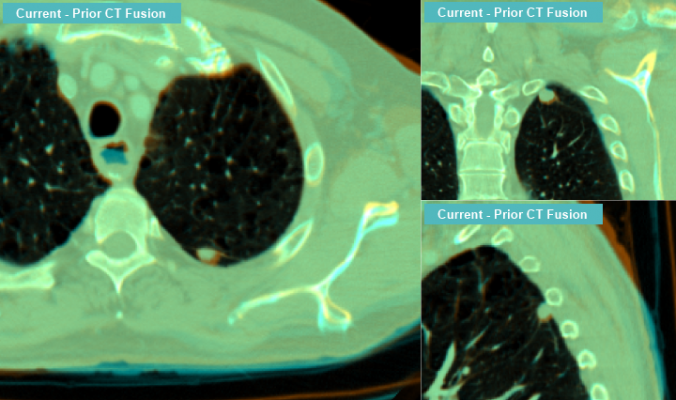

November 25, 2013 — Intelerad Medical Systems, a medical imaging picturing archiving and communication systems (PACS), radiology information systems (RIS) and workflow solutions developer, announced a technology partnership with Blackford Analysis, a provider of software products that accelerate comparison of medical images. The partnership will see Intelerad incorporate Blackford Analysis technology into its InteleViewer diagnostic imaging viewer.

Blackford Analysis’ Blackford MatchedCrosshairs and Blackford AutoSync functionality will enable InteleViewer users to provide instant comparisons of current and prior studies with a single click.

Blackford MatchedCrosshairs will enhance InteleViewer to allow users to simply click once on a location in any scan to instantly find the same location in multiple scans from different timepoints and/or different modalities (computed tomography [CT], magnetic resonance imaging [MRI] or positron emissions tomography [PET]).

Blackford AutoSync will provide InteleViewer with the ability to perform slice synchronization across multiple exams automatically, regardless of differences in acquisition protocol and patient positioning. This eliminates the often tedious step of manually syncing studies with multiple priors.